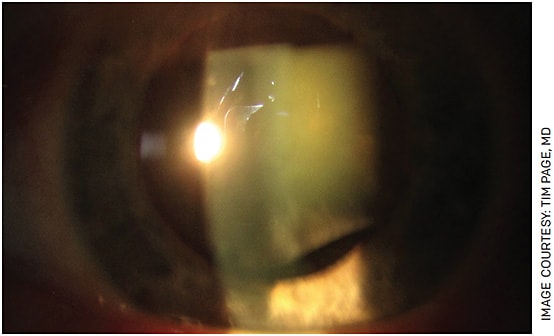

One of the reasons complex cataract cases take more time and require more resources is that they are technically more challenging and aren’t as predictable as routine cataract surgery. A surgeon may not know what kind of zonular support the lens will have, or, if a penetrating injury has a ruptured posterior capsule, they might encounter a never-ending fountain of vitreous (Figures 1 and 2). With many patients on alpha-1 antagonists, despite the use of intracameral agonists and pupil expansion rings, we still encounter cases in which the iris will prolapse through the paracentesis the moment it is made, creating a complication before we even get started.